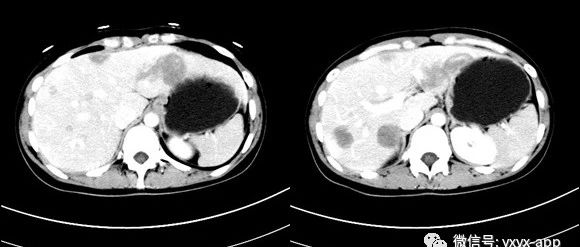

医学影像 yxyx-app 医学影像APP,打造伴随医生快速成长的影像学习社区。与影像园(Xctmr.com)一起提供最全面的影像案例库、基础(解剖、病理、影像诊断)知识、影像技术及考题等,为医生提供最佳的医学影像参考。【所属科室】消化科【基本资料】患者,女,22岁【主诉】发现肝脏占位17月【现病史】患者17月前于外院体检时,实验室检查:HBsAg+、抗-HBe、抗-HBc-IgM阳性;肝功正常; AFP、CEA均正常。腹部 B超:肝脏回声增粗、不均质,未进行相关治疗。近日患者再次就诊,查AFP、肝功、血常规正常。...